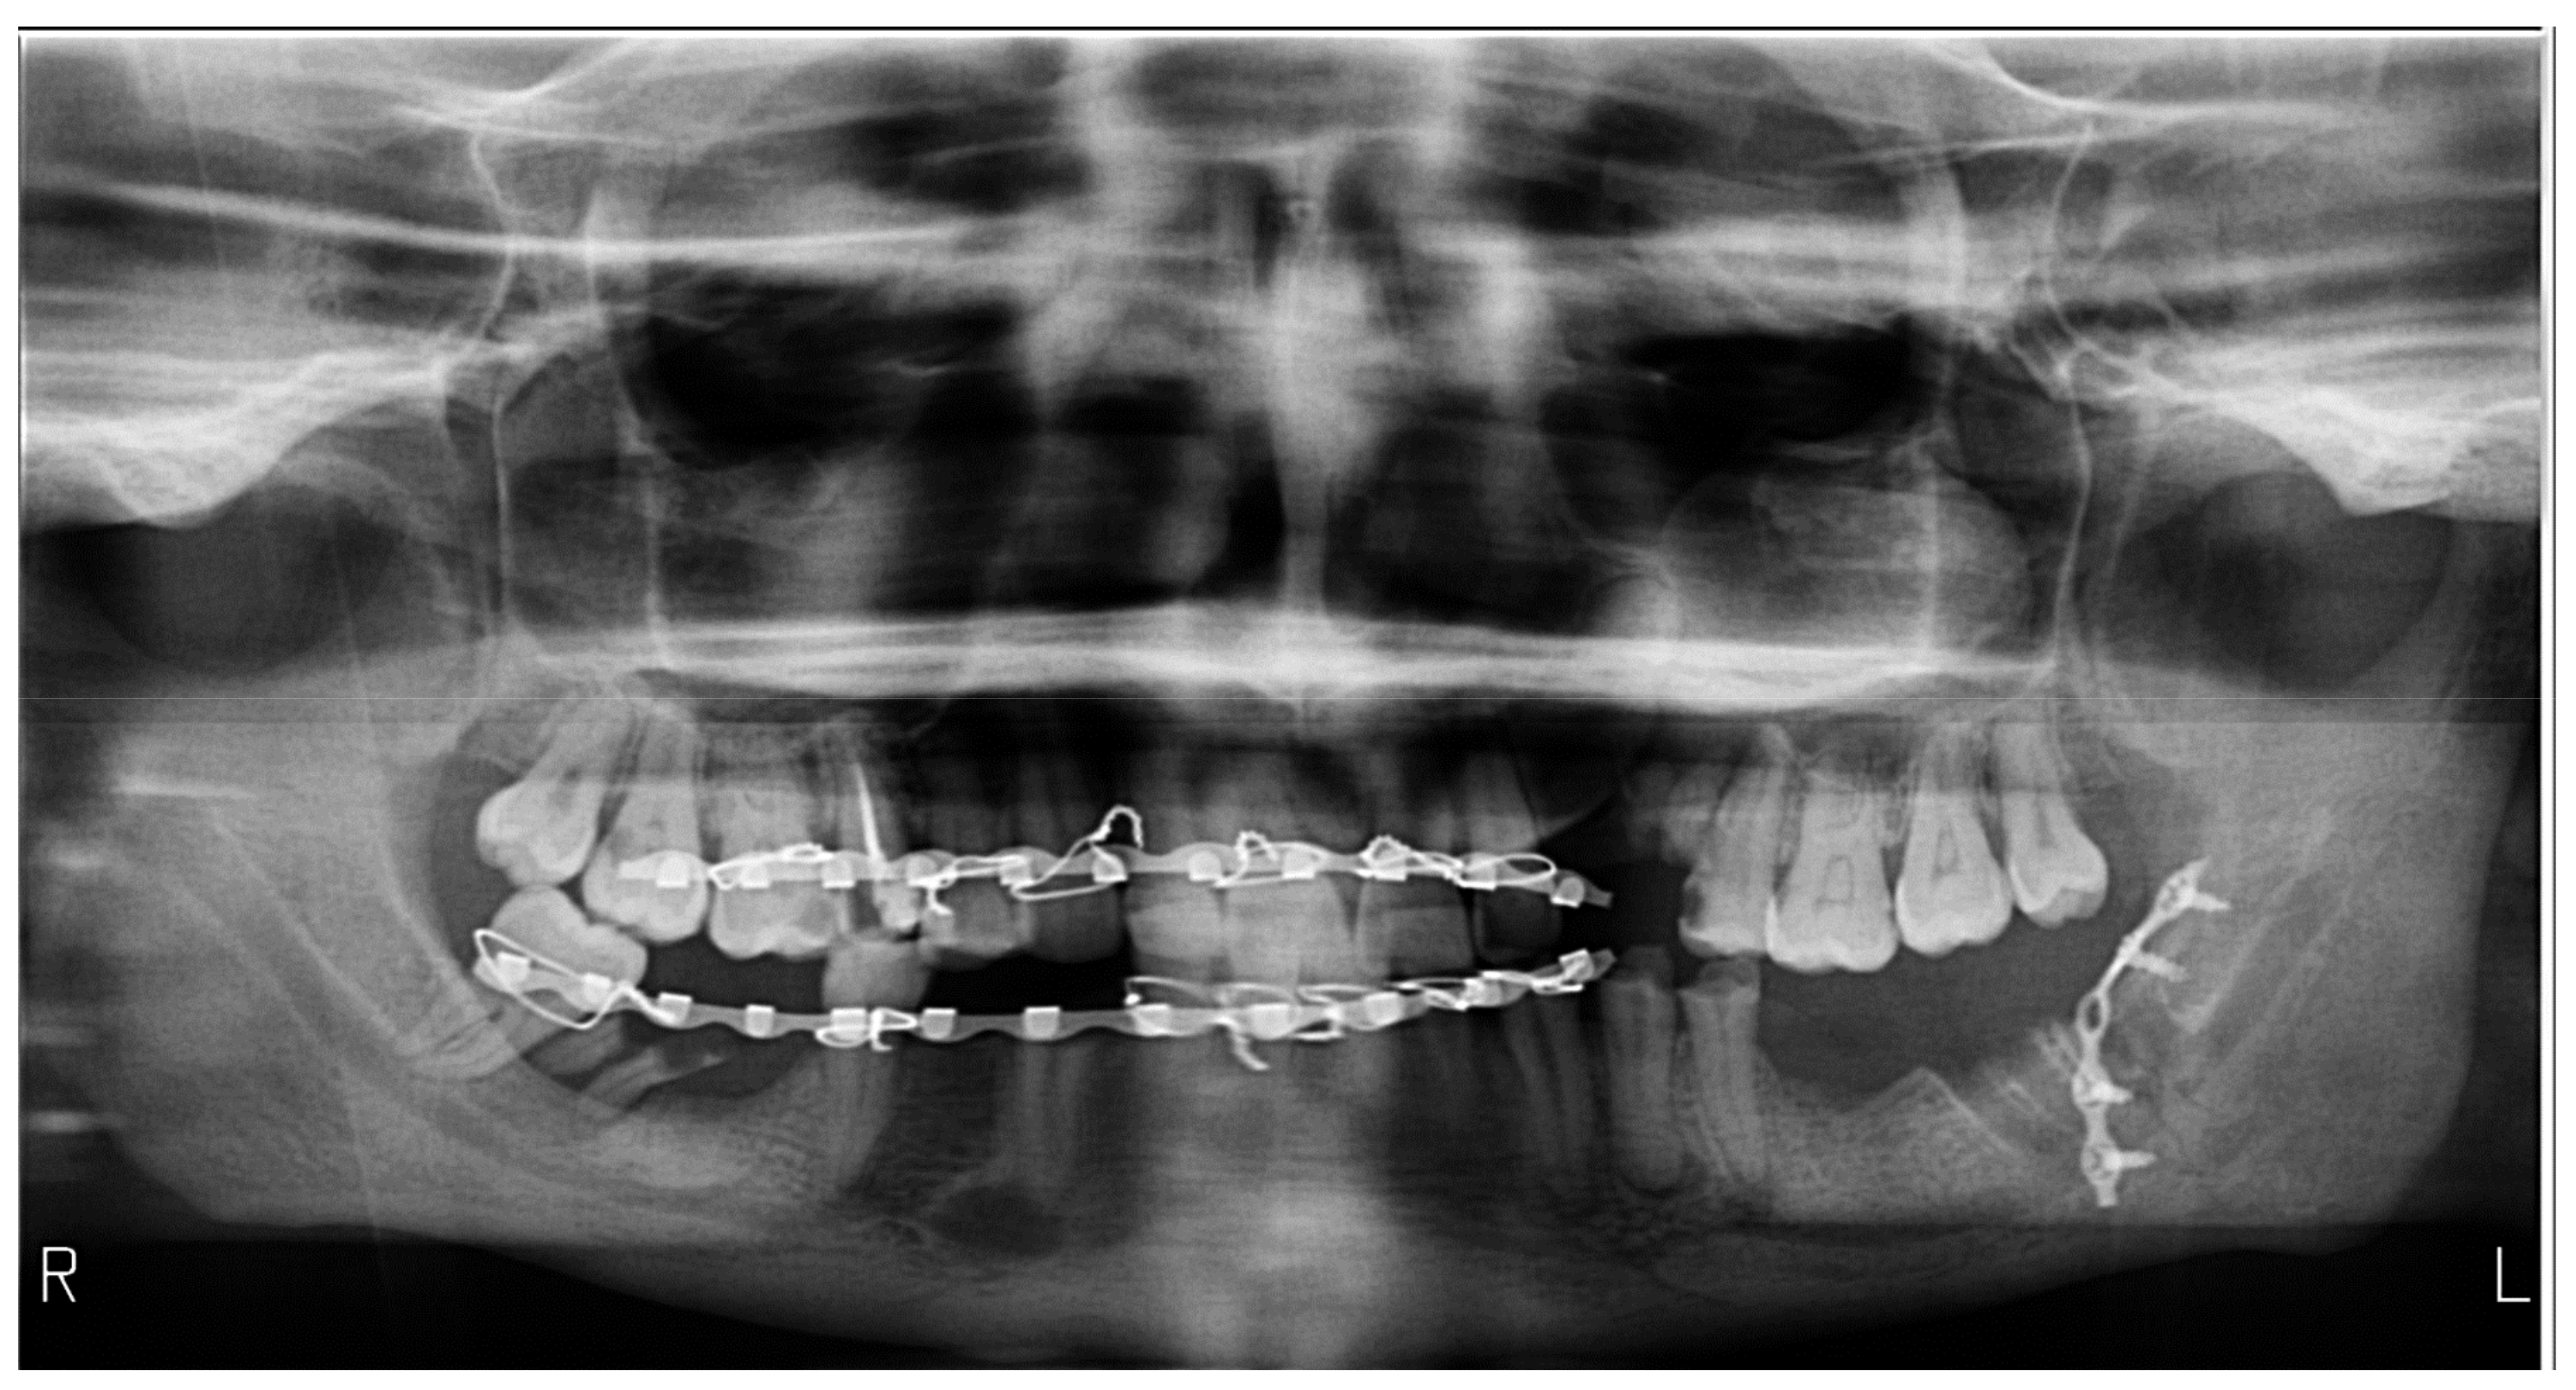

| Radiographs with bimaxillary immobilization errors | 23 | 76.66 | 62.16 | [59.07–88.21] * |